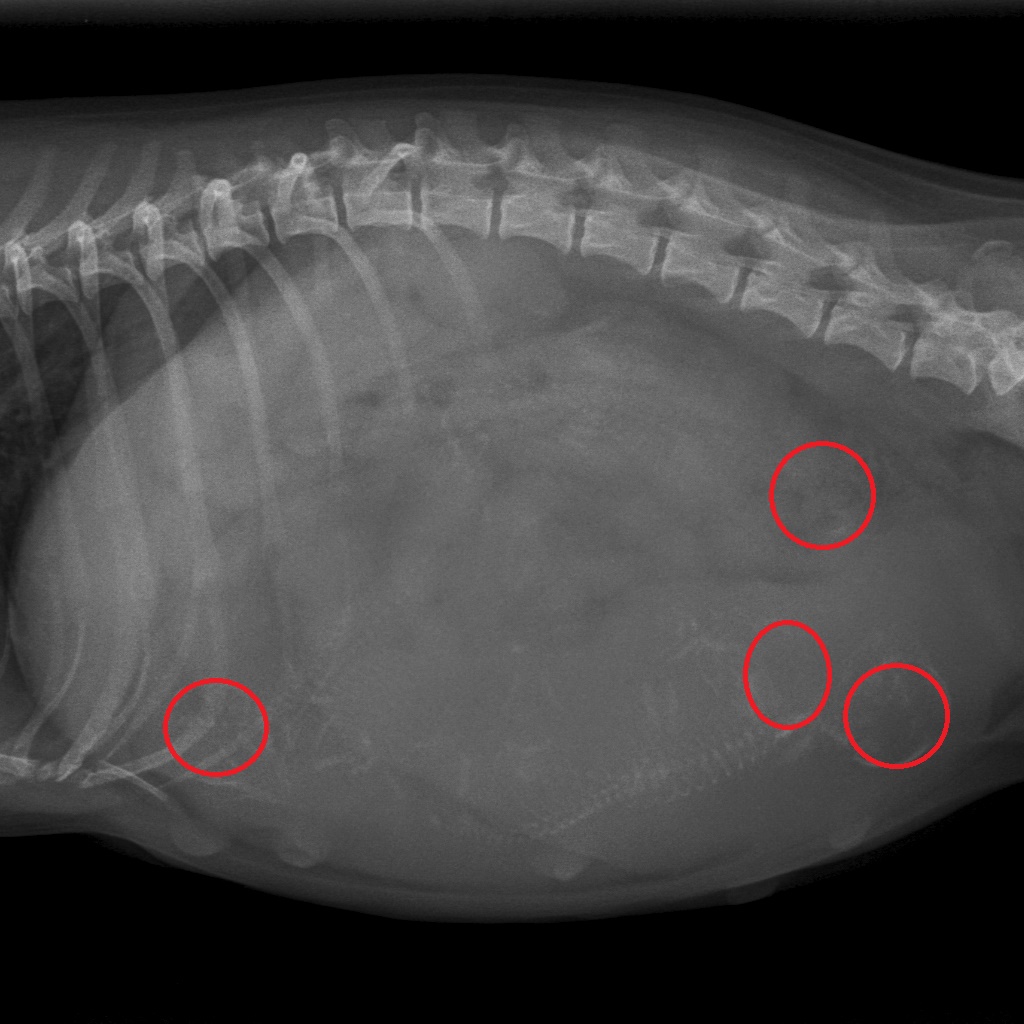

Miss kelly is drachtig. Het chihuahua-teefje van anderhalf jaar kwam op 4 mei op de praktijk voor een röntgenfoto. Haar baasjes wilden namelijk graag weten hoeveel pups ze in haar buik had. Op onderstaande foto's ziet u dat we vier pups tellen, de rode cirkels zijn de kopjes van de ongeboren pups.